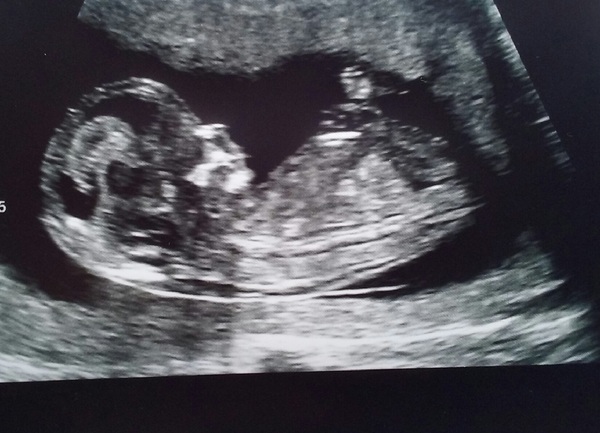

So I've attached mine from Tuesday. Smile Let's see some more!